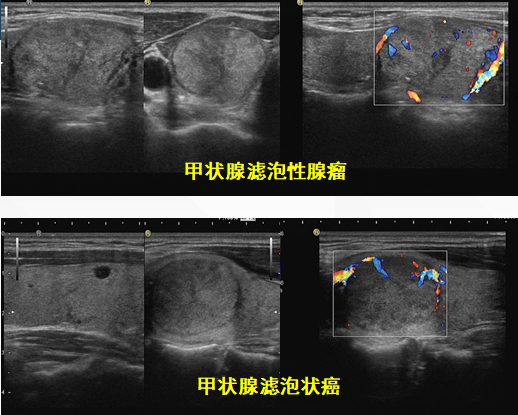

3.甲状腺滤泡状癌的超声表现有特征性吗?超声诊断靠谱吗?